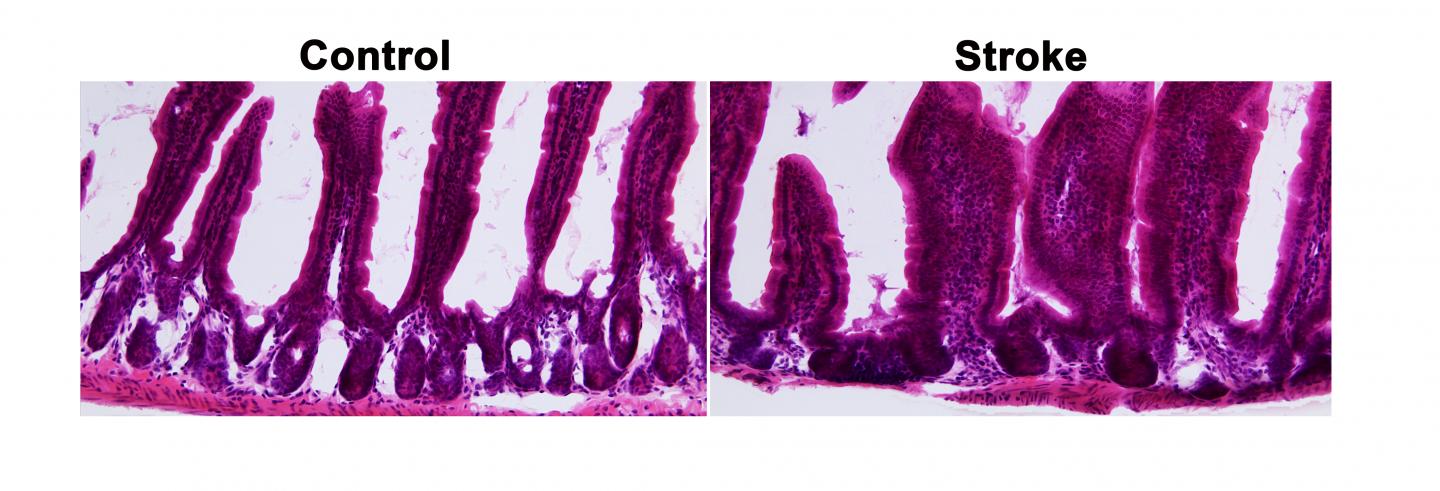

The gut-brain axis seems to distribute a stroke’s effects in another way, too. The research team discovered that a stroke can cause intestinal abnormalities. Under magnification, the intestinal tissues of healthy models resembled an orderly colony of coral. The branches of “coral” were actually villi—tiny projections that increase the surface area of the intestinal wall and multiply the amount of nutrients it can absorb.

But in post-stroke models, the intestinal tissue looked scrambled, even a month after researchers triggered the stroke. “There’s disorganization here,” Brichacek said. “There’s also less space between the villi to allow nutrients to move around.” Poor circulation of nutrients can lead to compromised stroke recovery.